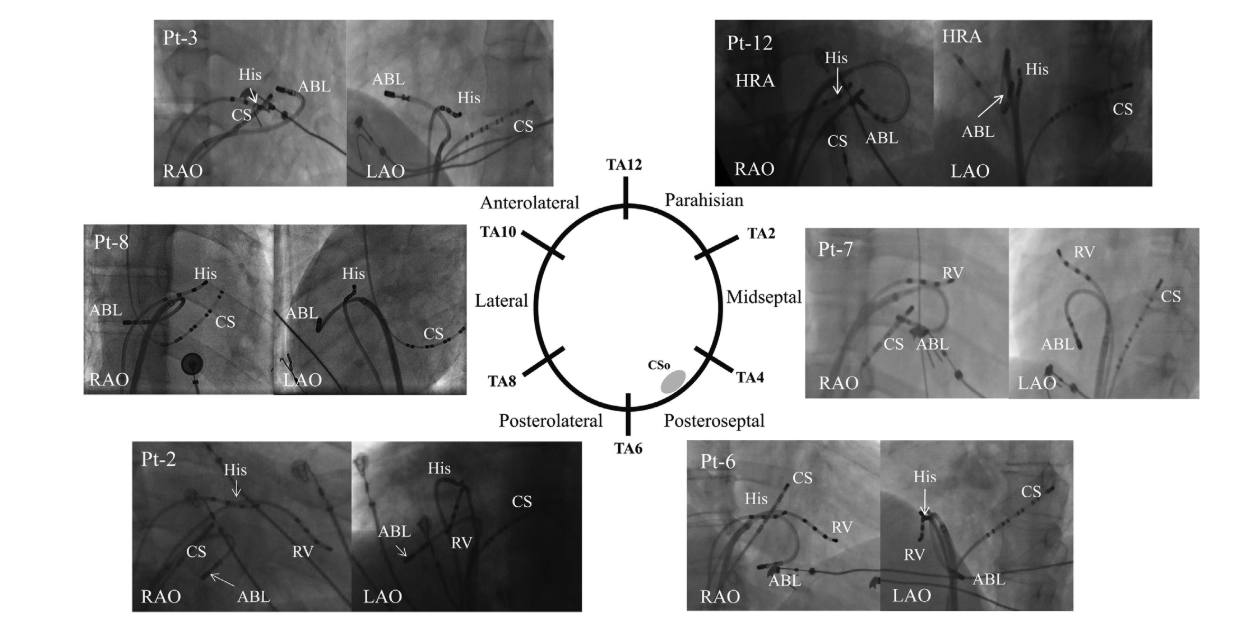

Non annular location of AP

fig2.jpg

fig3.jpg